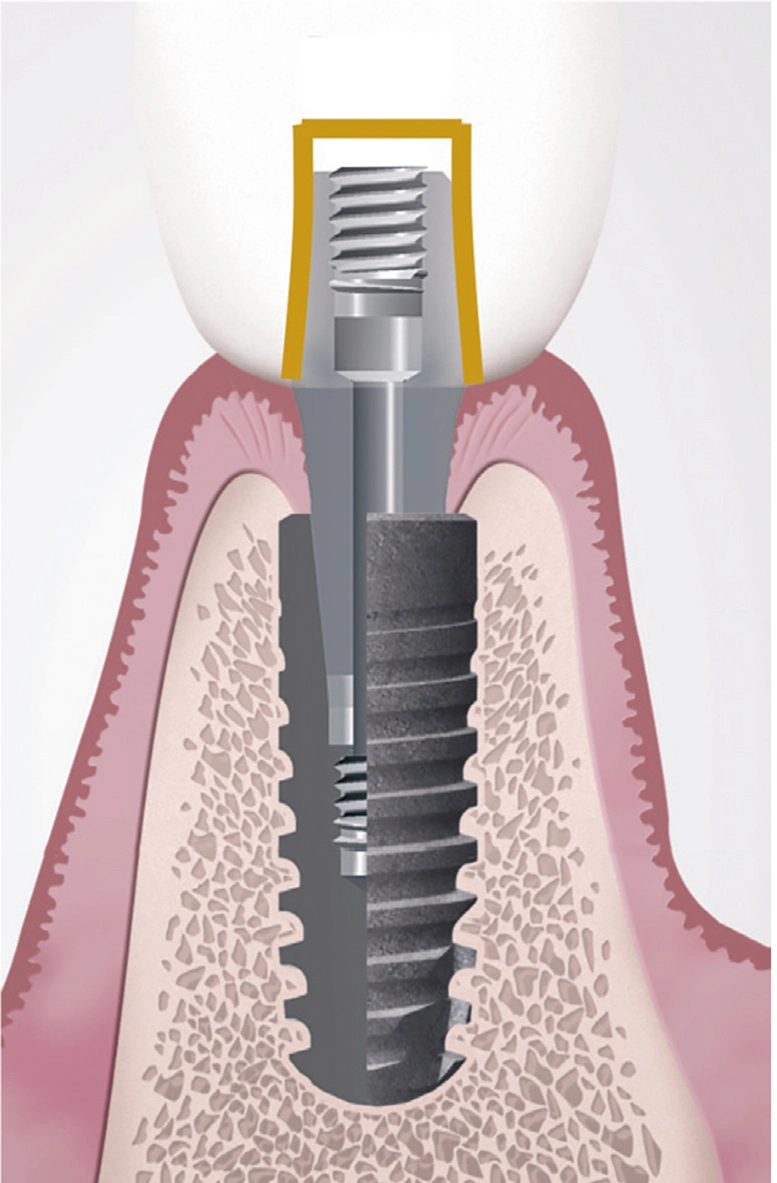

Verschraubung der mit dem Abutment verklebten Restauration direkt im Implantat

Ein weiterer Vorteil ist darin zu sehen, dass nur eine Verschraubungseinheit vorliegt, deren Schraubenkopf zudem tief an der Basis des Abutments angeordnet ist und einen relativ kleinen Durchmesser aufweist. Damit lässt sich der okklusale Zugang in gleicher Weise wie oben erwähnt verschließen und ein günstiger kosmetischer Effekt erzielen (Abb. 5a-d).